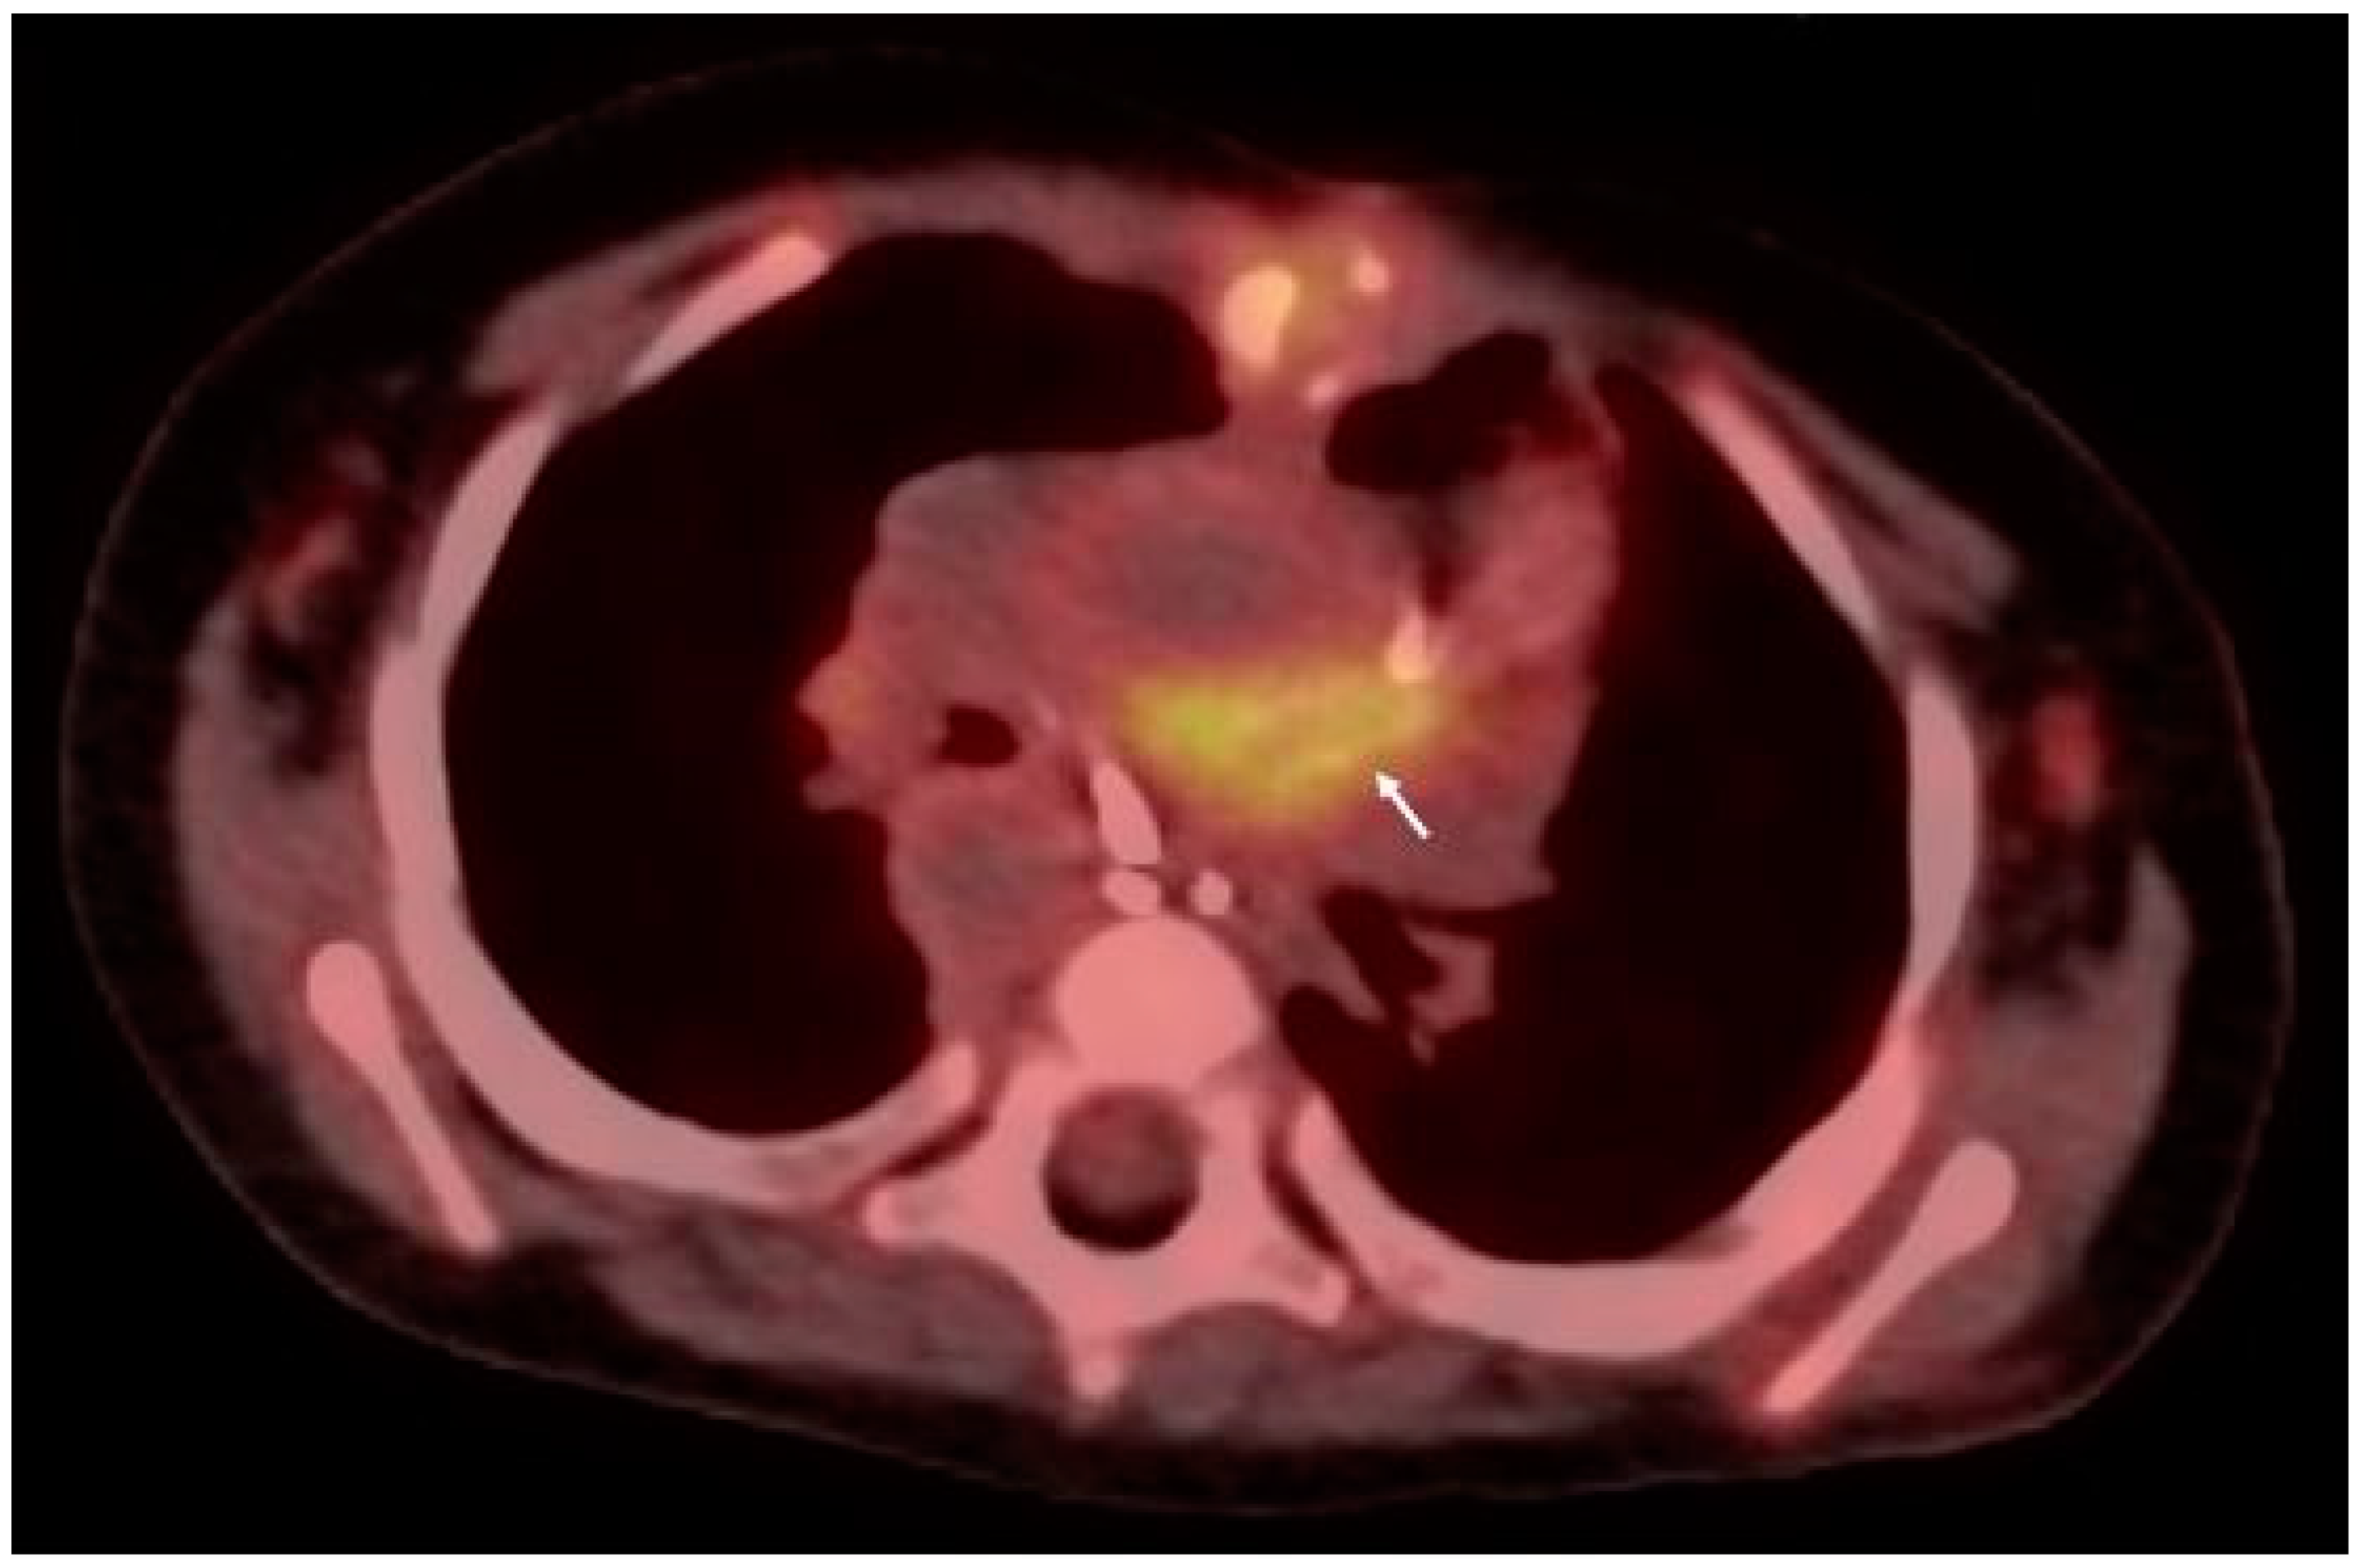

- Joye, R.; Ceroni, D.; Beghetti, M.; Aggoun, Y.; Sologashvili, T. Fulminant Infective Endocarditis Due to Kingella kingae and Several Complications in a 6-Year-Old Girl: A Case Report. Front. Pediatr. 2021, 9, 707760. [Google Scholar] [CrossRef] [PubMed]

- Duval, X.; Le Moing, V.; Tubiana, S.; Esposito-Farese, M.; Ilic-Habensus, E.; Leclercq, F.; Bourdon, A.; Goehringer, F.; Selton-Suty, C.; Chevalier, E.; et al. Impact of Systematic Whole-body 18F-Fluorodeoxyglucose PET/CT on the Management of Patients Suspected of Infective Endocarditis: The Prospective Multicenter TEPvENDO Study. Clin. Infect. Dis. 2021, 73, 393–403. [Google Scholar] [CrossRef] [PubMed]

- Wang, T.K.M.; Sanchez-Nadales, A.; Igbinomwanhia, E.; Cremer, P.; Griffin, B.; Xu, B. Diagnosis of Infective Endocarditis by Subtype Using 18F-Fluorodeoxyglucose Positron Emission Tomography/Computed Tomography: A Contemporary Meta-Analysis. Circ. Cardiovasc. Imaging 2020, 13, e010600. [Google Scholar] [CrossRef]

- Meyer, Z.; Fischer, M.; Koerfer, J.; Laser, K.T.; Kececioglu, D.; Burchert, W.; Ulrich, S.; Preuss, R.; Haas, N.A. The role of FDG-PET-CT in pediatric cardiac patients and patients with congenital heart defects. Int. J. Cardiol. 2016, 220, 656–660. [Google Scholar] [CrossRef]